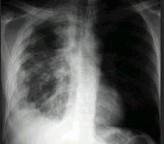

问题 男,40岁,胸痛胸闷2月,胸片如图,最可能的诊断为()

选项 A.右侧恶性胸膜间皮瘤 B.右侧胸腔积液 C.右侧包裹性积液 D.右侧良性胸膜间皮瘤 E.右侧胸膜增厚

答案 A